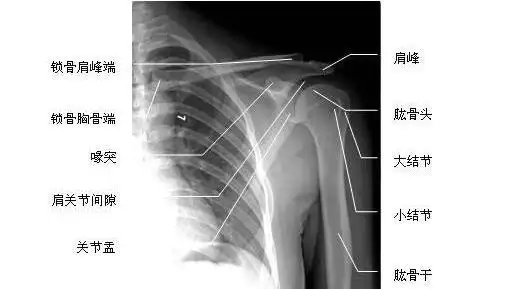

肩关节正位-x线片

图片尺寸512x289

ap in internal rotation肩胛骨内旋正位六ap view 肩关节正位(胸片位